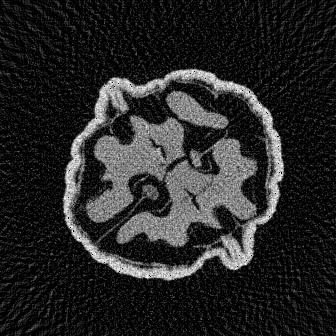

The numerical results are summarized in Table 1. These are evaluated in terms of peak signal-to-noise ratio (PSNR) and structural similarity index (SSIM) considering three different sampling settings, with different sparsity levels , angles, and noise set to 1% AWGN. It is evident that our method, TomoSelfDEQ, outperforms the competing approaches in terms of both PSNR and SSIM. In Fig. 1, we report the results obtained with the different methods considering 64 (top row), 32 (middle row) and 16 (bottom row) angles. We can see that with TomoSelfDEQ was able to reconstruct sharp and neat boundaries, even though some finer details are lost due to over-smoothing in certain regions. In addition, TomoSelfDEQ accurately reconstructs constant patches, without adding any significant artifacts and it proves to be stable with respect to the reduction of angles. On the other hand, FBP reconstructions are noisy and show an increasing number of streaking artifacts as the number of angles decreases. In the TV regularized reconstructions, the staircasing behavior is evident, and the sharpness of the boundaries deteriorates as the number of angles decreases. Sparse2Inverse produces reconstructions with clear artifacts, particularly when only 16 angles are considered.

Similar consideration can be drawn for the reconstructions in Fig. 2, where we show reconstructions of different walnut slices in the most challenging setting, i.e., with 16 angles. From the close-ups it is clear that Sparse2Inverse introduces numerous noisy artifacts, compromising the reconstructions, while TomoSelfDEQ better preserves objects shapes, significantly reducing noise presence. A note is, however, in order on the comparison with Sparse2Inverse. While both methods share key ideas such as operating in both image and projection domains, computing losses in the projection domain, and avoiding explicit nullspace assumptions, TomoSelfDEQ differs fundamentally in several important aspects. First, while Sparse2Inverse uses a standard U-Net architecture, our method leverages DEQ to implicitly represent an infinite-depth network. Second, TomoSelfDEQ provides theoretical guarantees about matching supervised performance, while Sparse2Inverse relies primarily on empirical validation. These theoretical and architectural advantages translate into practical improvements, as demonstrated in our numerical results where TomoSelfDEQ consistently outperforms Sparse2Inverse across different undersampling rates (cf. Table 1).